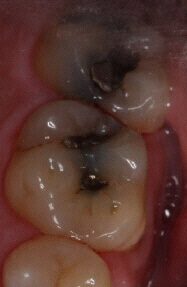

In December 2018, a male patient underwent a successful dental procedure for tooth-colored fillings by Dr. Jeffrey A. Weller in Chicago, IL. The patient experienced a positive outcome post-treatment, expressing satisfaction with the clinical service received. The procedure significantly improved the patient’s dental health, enhancing both function and aesthetics. Dr. Weller’s expertise and the quality of care provided contributed to a favorable experience for the patient.

Before